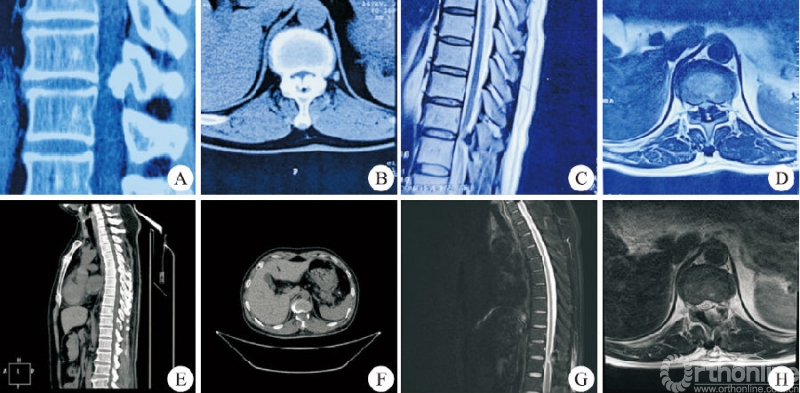

所有患者的手术由同一位术者完成,手术均顺利完成,无硬膜外血肿、切口感染及术后瘫痪者。37例患者中男14例,女23例;年龄31~82岁,平均(57.6±11.8)岁。上胸段(T1−T4)1例,中胸段(T5−T9)7例,下胸段(T10−T12)29例。24例采用俯卧位,13例采用侧卧位。平均住院时间(7.2±1.6)d,平均手术时长(96.5±20.0)min。平均出血量(41.9±10.8)mL。24例俯卧位手术患者均为OLF,做“漂浮”处理的3例,2例患者术中硬膜破裂(图3)。13例侧卧位手术患者中TDH3例,OPLL5例,OLF+OPLL5例,做“漂浮”处理的1例,2例患者术中硬膜破裂(图4)。术后影像学检查示椎管减压充分,致压物被完全去除。

女,38岁,T11−T12后纵韧带骨化,行侧卧位经皮内镜可视化环锯椎管减压术。A、B:术前CT矢状位和横断位示T11−T12鸟嘴型后纵韧带钙化;C、D:术前MRI示脊髓腹侧严重受压;E、F:术后CT矢状位和横断位示钙化的后纵韧带完全去除单侧关节突关节成形;G、H:术后MRI示脊髓腹侧致压物完全去除硬膜充分膨胀。图4 T11−T12侧卧位胸椎后入路术前与术后影像学资料